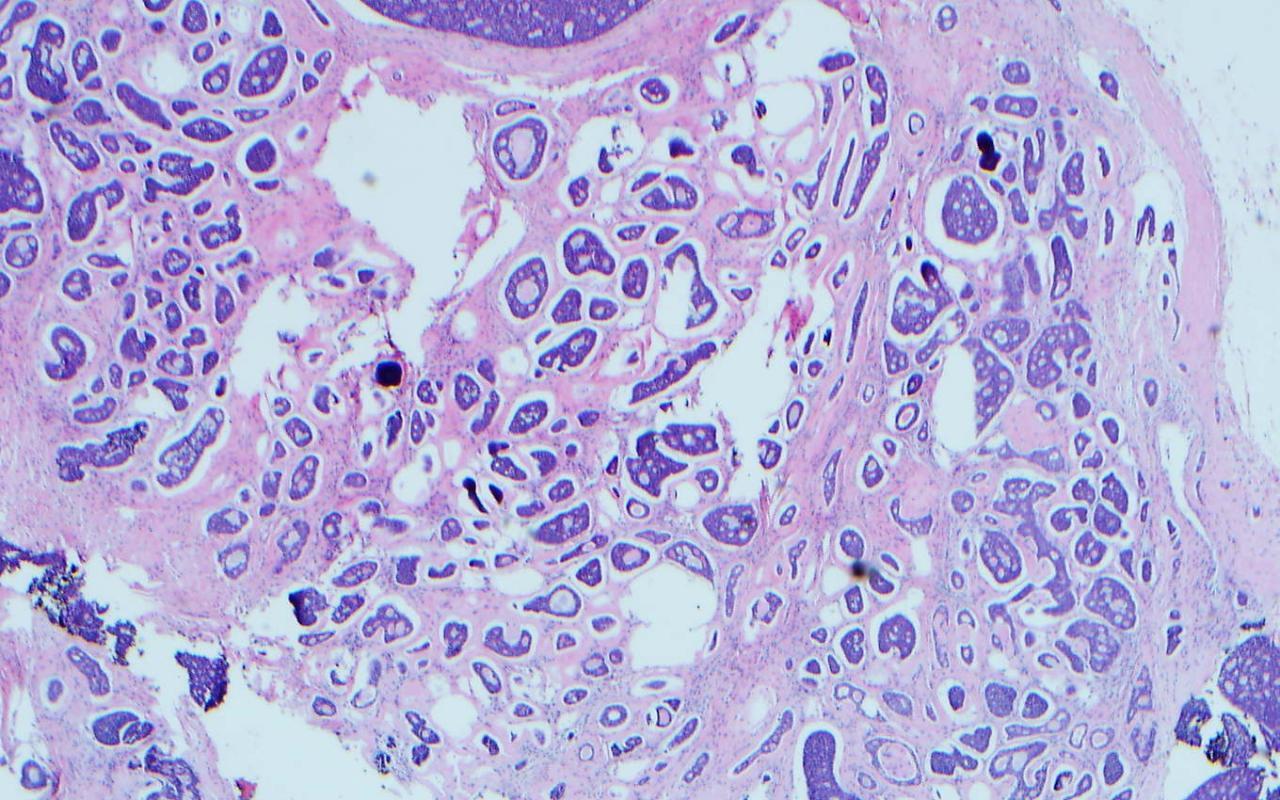

39. A 62-year-old man presents a 1.8cm pink, friable mass on his right upper back. A full skin exam shows no other suspicious lesions and no palpable lymph nodes. A shave biopsy is done and the H+E and CK20 immunohistochemistry are shown in the images. Which of the following is the best treatment to proceed with next?

Correct choice:D. Wide local excision with sentinel lymph node biopsy Explanation: The clinical and pathological findings are consistent with a Merkel cell carcinoma. The preferred treatment for a tumor on the trunk without clinically apparent lymphadenopathy is wide local excision (1-3 cm margins) and sentinel lymph node biopsy. If the lymph node biopsy is positive, then the patient will likely require radiation therapy. For lesions >2cm, some clinicians will not perform a sentinel lymph node biopsy since radiation therapy is indicated regardless, given the high risk of lymph node metastasis.